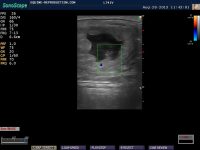

By day 23 or so (and earlier if color doppler ultrasound is used), a heartbeat should begin to be visible during the ultrasound process. the orange and blue dots on the embryo proper visible in this image are color doppler imagery indicating direction of blood flow.